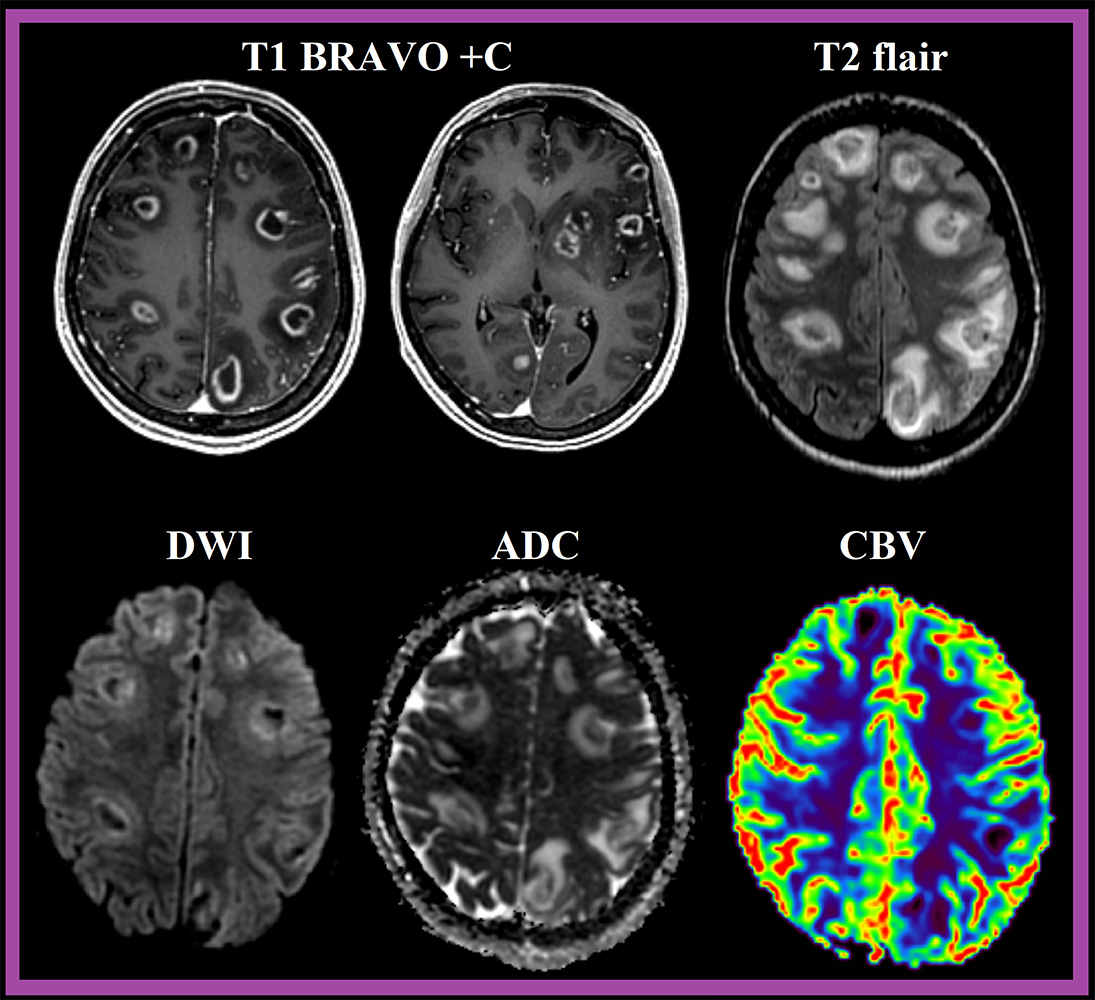

При МР-исследовании типичным признаком церебрального токсоплазмоза является знак концентрической мишени (concentric target sign), визуализируемый в Т2\T2flair последовательности в виде поражений, имеющие в своей структуре нескольких концентрических колец с попеременным гипер- и гипоинтенсивным сигналом.

На постконтрастных сериях Т1, очаги демонстрирую кольцевидный паттерн контрастирования с характерным знаком мишени (target sign). После МР-визуализации, как правило, биопсия не требуется.